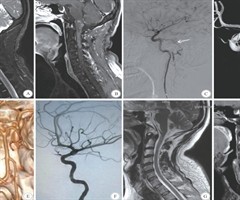

CognardTypeV硬脑膜动静脉瘘的诊断与治疗

【摘要】目的本研究旨在探讨颅内硬脑膜动静脉瘘(DAVF)向脊髓表面静脉引流(即Cognard Type V型DAVF)的临床特点、影像学特征及诊疗方法。方法回顾性分析2017年1月—2025年1月四川大学华西医院神经外科收治的12例Cogn...